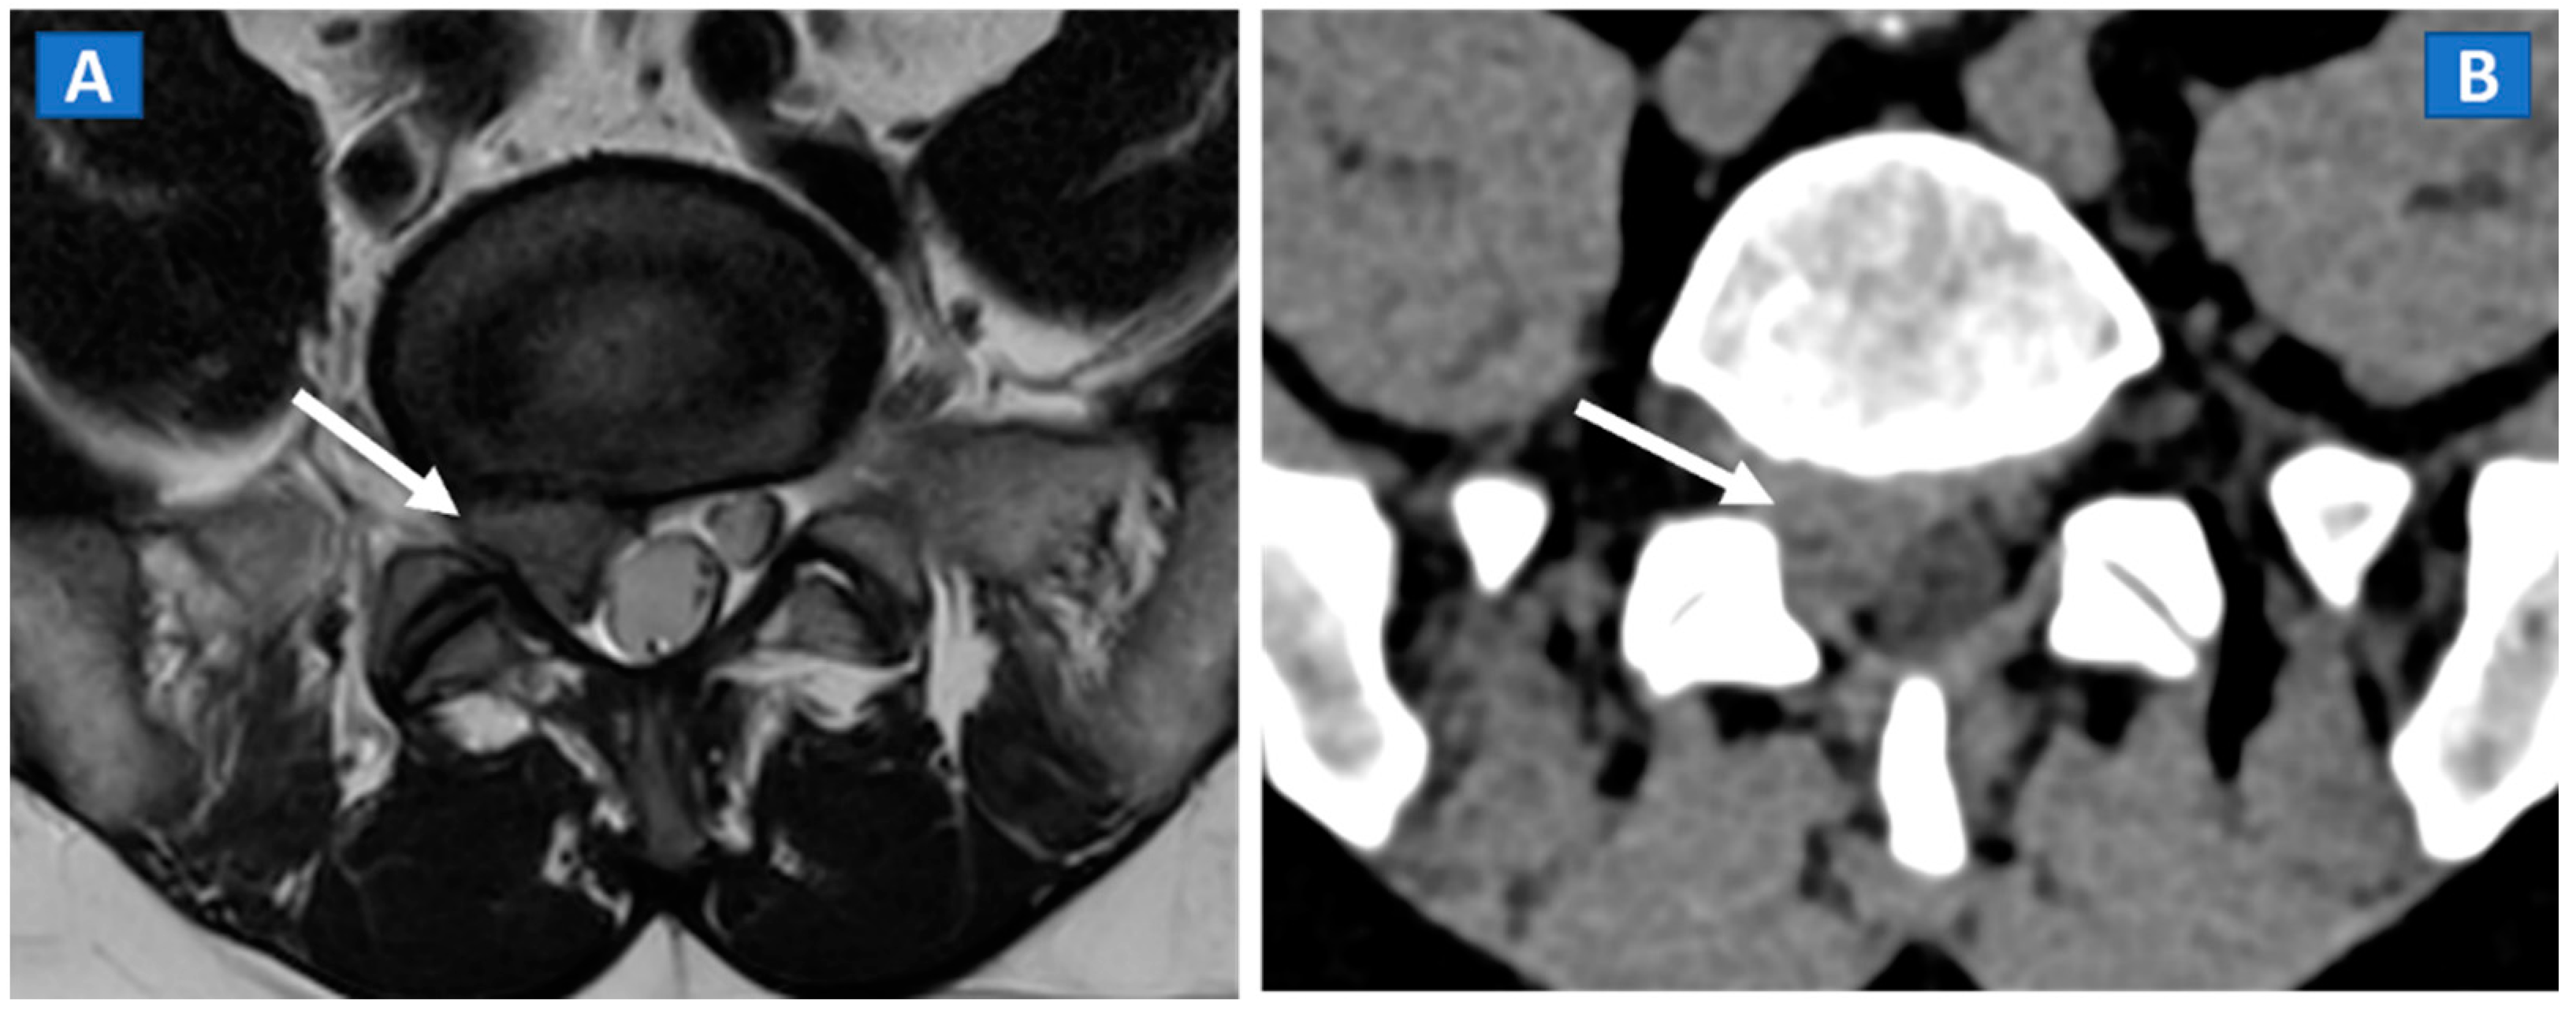

A 46-year-old male with non-traumatic, acute right sciatica pain. A large, right postero-lateral disk herniation (arrow) can be recognized at L5-S1 level both on the axial T2-weighted MR image (A) and on the corresponding axial 1 mm reconstructed CT image with a soft tissue window (B).